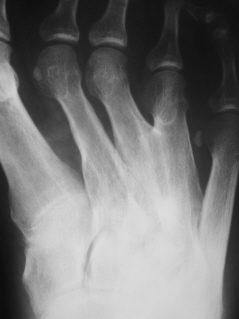

Иллюстрация 3. Фрагмент рентгенограммы области патологического синостоза, произведенной в косой проекции с увеличением.